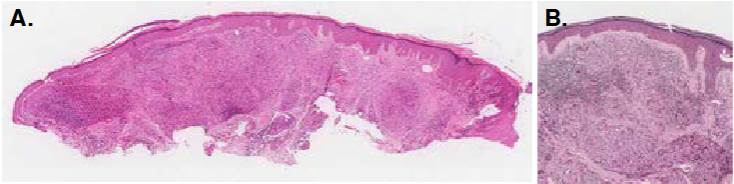

Figura 1 A. Imagen panorámica de la biopsia. Hay acantosis leve y, en la dermis, inflamación granulomatosa difusa. Hematoxilina y eosina, 1X. B. Epidermis normal, separada de la dermis por una delgada banda colágena. Granulomas dérmicos particularmente ricos en células gigante multinucleadas de tipo Langhans. Hematoxilina y eosina, 6X.